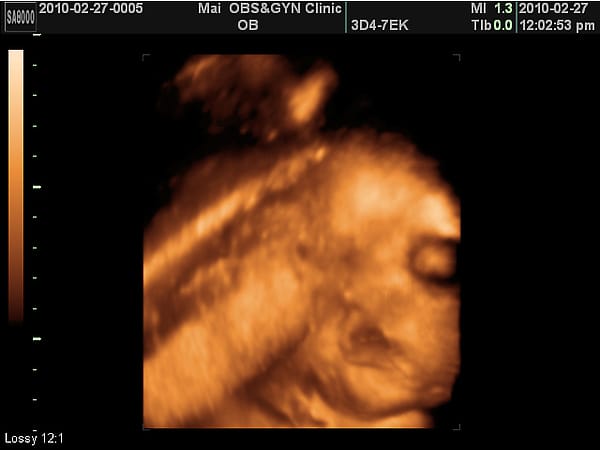

34W第七次產檢報告

小老虎第七次產檢,驗尿ok,血壓ok,母親體重63.6KG。 小老虎上次產檢1500公克,這次2050公克,這四周母體因為深受失眠之苦居然瘦了1.2KG,使得整體體重控制在10KG左右。 血壓:85/53 心跳:101 上次B肝抽血檢驗OK。 下回產檢要檢查乙型鏈球菌,自費項目。   目前小老虎已就定位,這個位置羊水不夠多看不太清楚小老虎,但是呢,看起來眼窩黑黑滴,嘴唇厚 […]…